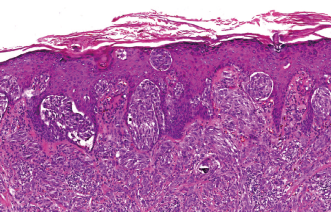

葡萄糖转运蛋白3在皮肤鳞状细胞癌中的表达及其对A431细胞增殖、侵袭及迁移的影响

王媛 王艺萌 吴雯婷 李婷婷 王冠钰 张春雷

摘要 ( 409) PDF (26147 KB) ( 3)

2023, Vol.56(5): 421–427   doi: 10.35541/cjd.20220770